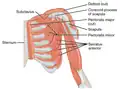

Subclavius (labeled top left) — frontal view

Subclavius (labeled top left) — frontal view